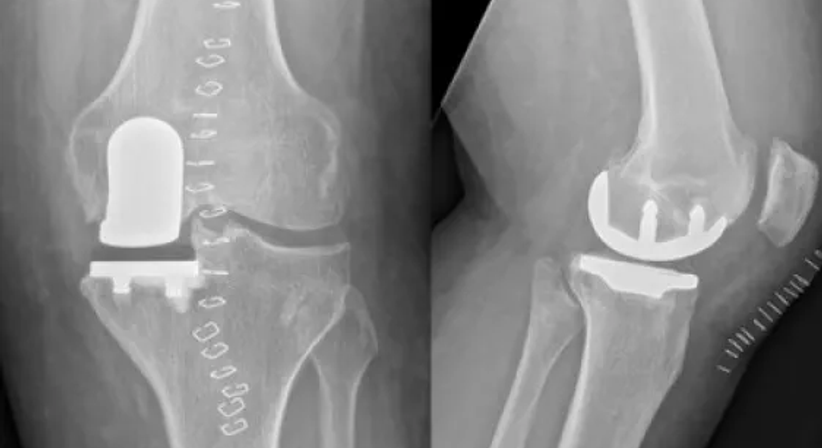

Ein künstliches Kniegelenk wird in der Regel dann notwendig, wenn eine Abnützung des Gelenkknorpels (Arthrose) vorliegt oder das Kniegelenk aufgrund einer Knieverletzung dauerhaft geschädigt ist.

• Totalendoprothese

Mithilfe einer Knietotalendoprothese (kurz Knie-TEP) kann das abgenützte Kniegelenk durch spezielle Oberflächenimplantate vollständig ersetzt werden. Die heutigen modernen Implantate sind sehr langlebig und weisen eine hohe Stabilität auf. Sie fühlen sich wie das eigene Kniegelenk an und ermöglichen dem Patienten auch bei gestrecktem Bein einen sicheren Stand.

• Halbschlittenprothese

Mit einer Halbschlittenprothese wird nicht das ganze Kniegelenk, sondern nur der abgenützte, verschlissene Anteil (entweder der innere, äußere oder hinter der Kniescheibe gelegene Teil) endoprothetisch ersetzt. Sämtliche gesunde Strukturen des Gelenks werden geschont und bleiben anatomisch unverändert. Der Vorteil beim Einsatz einer Halbschlittenprothese liegt in der verkürzten Operations- und Rehabilitationszeit. Aufgrund der rascheren Genesung kann die volle Mobilität in relativ kurzer Zeit wiedererlangt werden.